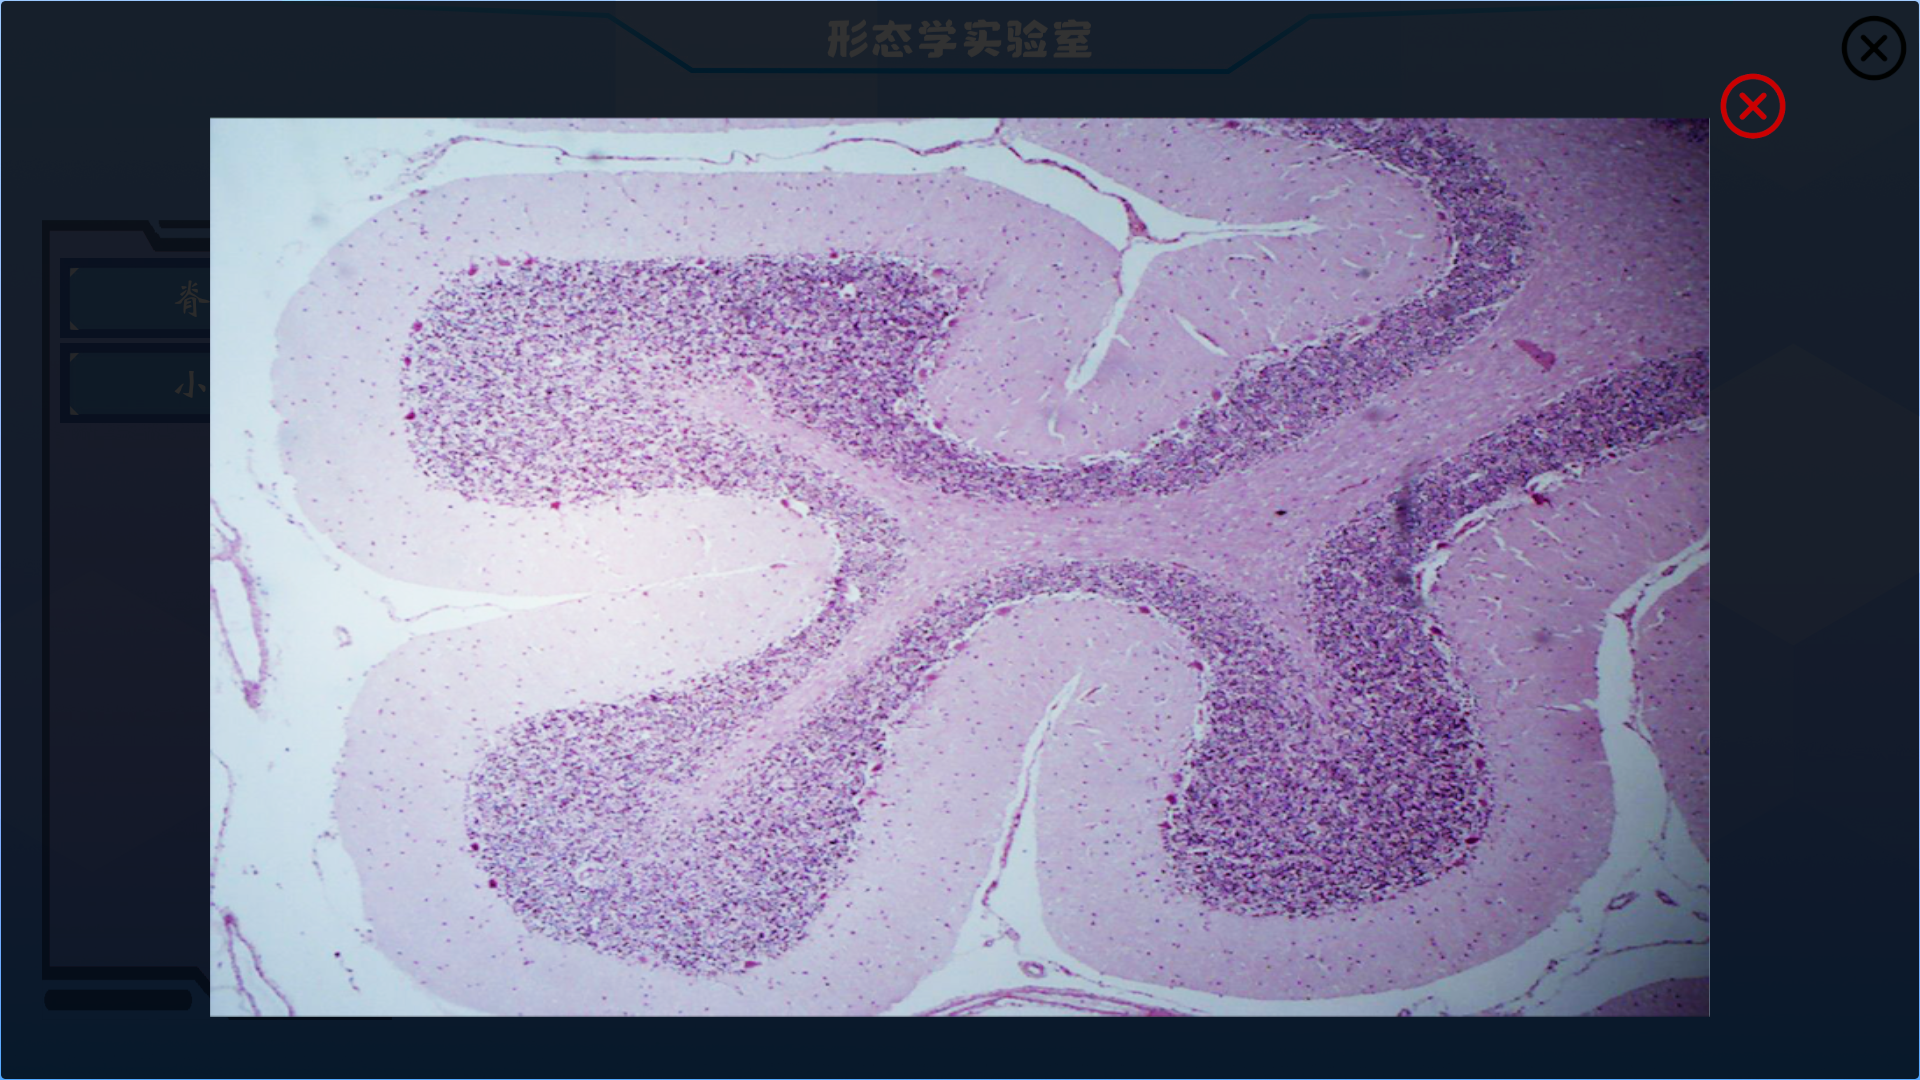

功能集成,目前包括人体解剖学教学、组织学胚胎学教学、介入手术教学、影像学教学等功能

本产品打破以往产品功能单一的局面,目前具有解剖教学、组胚教学、影像教学、模拟介入手术等功能

组胚教学模块内置了人体组织学与胚胎学常见光镜切片标本,您可以随时访问这些资源

以下是产品内截图实况